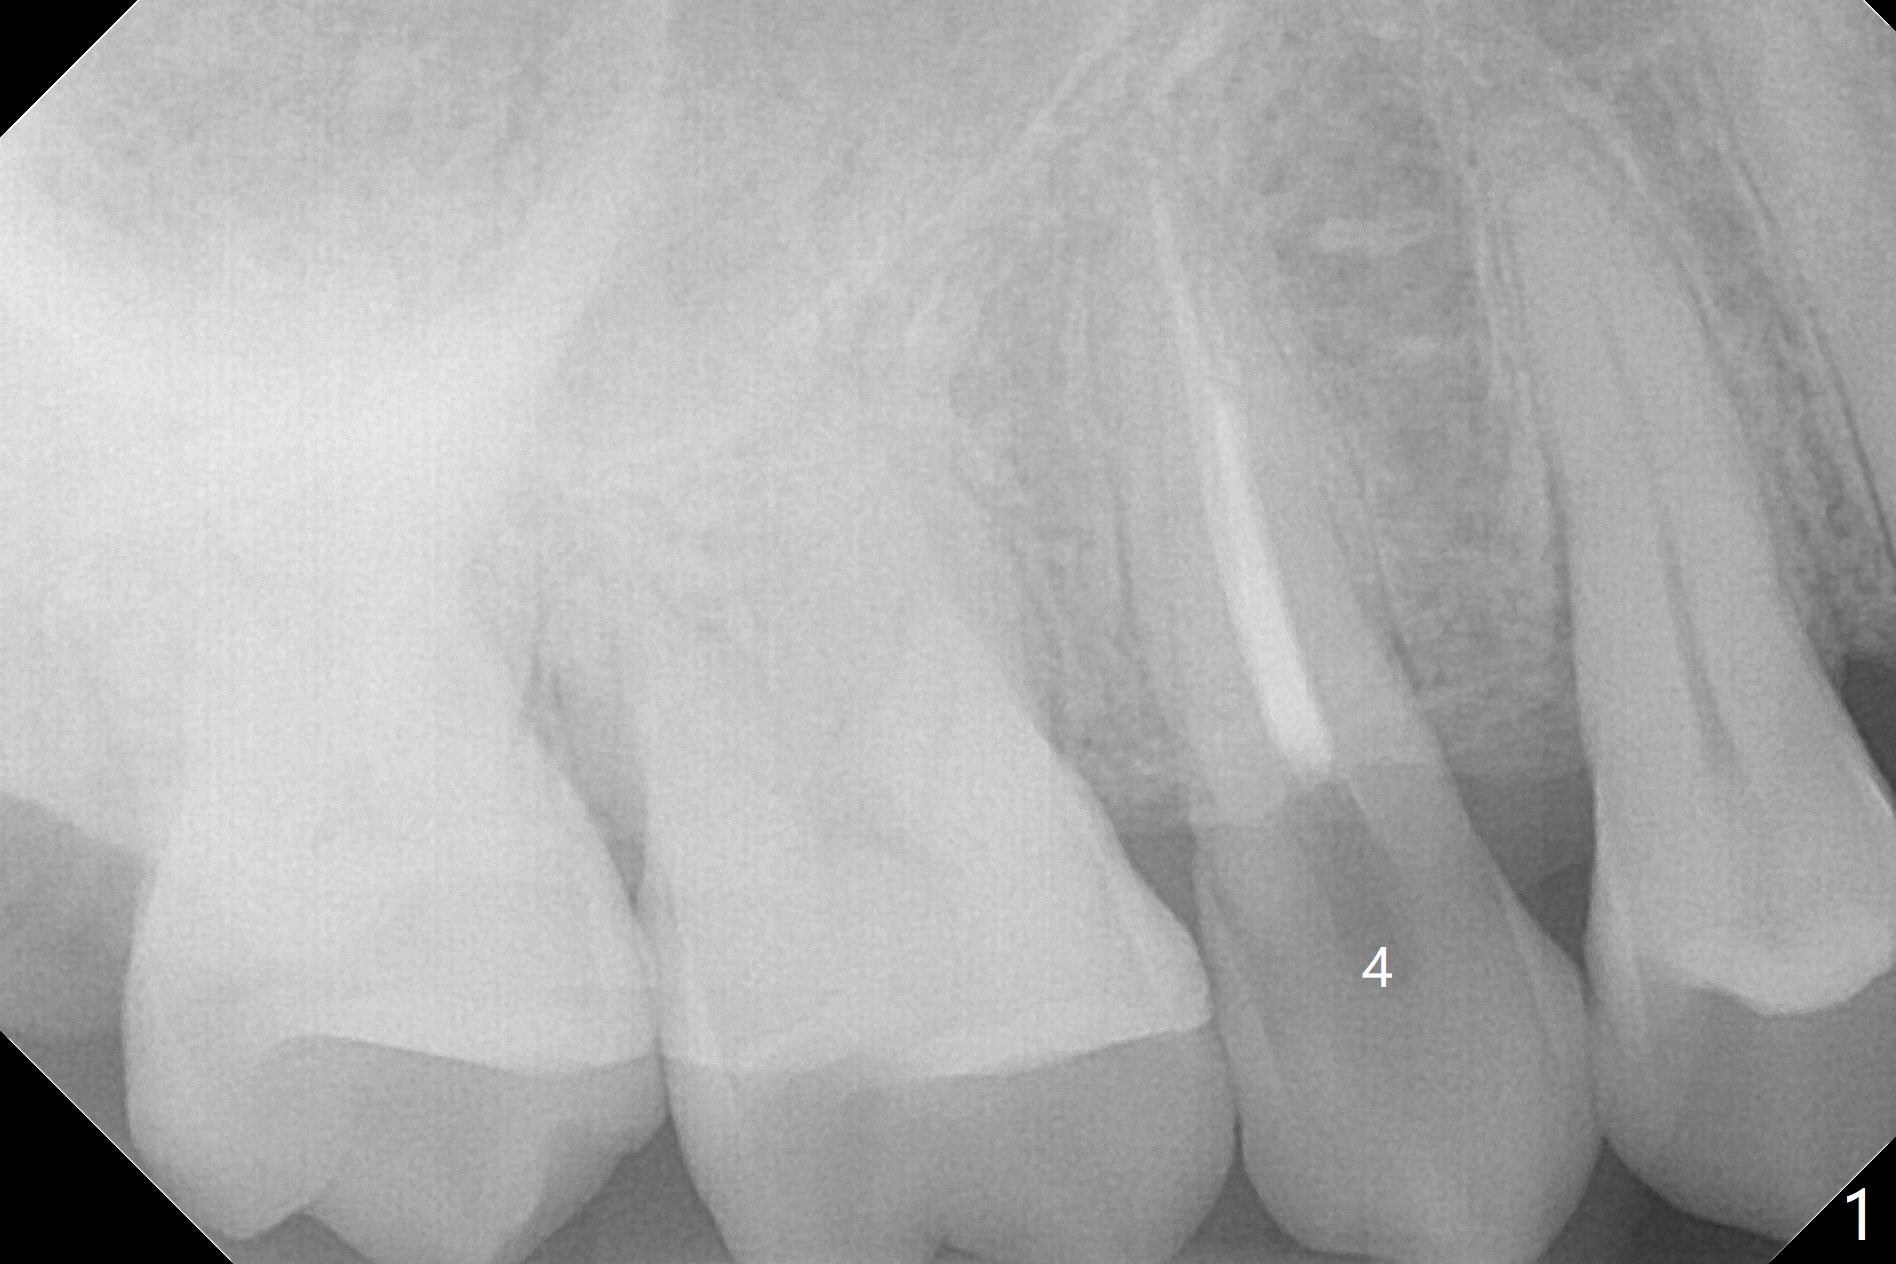

A 65-year-old man cracks 3 teeth in ~2 years (Fig.1,2 (#4,13,15)). The tooth #4 is symptomatic after RCT (Fig.1); it appears that the buccal canal is incompletely filled (data not shown). In fact an exam 1 month later shows that the symptomatic tooth is #2 (crack), while #4 is salvageable (Fig.8). The tooth #13 has palatal subgingival fracture with severe pain (Fig.2 with palatal defect). In fact the title of this case is incorrect). After extraction, allograft is placed (Fig.3 *) with 6-month membrane. In fact the bone graft is not packed into the apex of the socket; a condenser should have been used. The patient returns 3 days postop before leaving abroad. The 6-month membrane remains in place (Fig.4), while the ridge at #15 is minimally atrophic (Fig.5). The coronal lamina dura becomes indistinct 5 months postop (Fig.6). The bone graft remains in the socket. The distoapical portion of a 4x11.5 mm implant may be in the sinus (Fig.7).